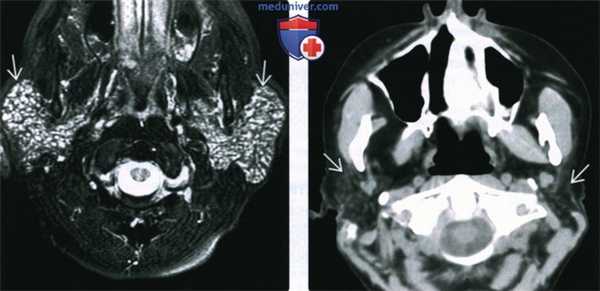

(Справа) МРТ Т2ВИ FS, аксиальная проекция. В обоих околоушных железах определяются гипереинтенсивные образования, которые представляют собой кистозное расширение протоков околоушной железы при синдроме Шегрена. Тем не менее, такая МР-картина неотличима от лимфоэпителиальных образований при ВИЧ. (Слева) КТ с КУ, аксиальная проекция. Жировая инволюция обеих околоушных желез, которые имеют многодольчатое строение. В толще желез множественные кальцификаты. Участки отечной железистой ткани, в которой встречаются фрагменты жировой клетчатки и кальцификаты, характерны для синдрома Шегрена.

(Справа) На аксиальной МРТ (Т2 ВИ FS) визуализируются многочисленные мелкие кисты, разбросанные в паренхиме обеих околоушных желез (картина множественных милиарных кист).

(Слева) МРТ Т2ВИ FS, аксиальная проекция. Ткань обеих околоушных желез полностью замещена бесчисленными мелкими кистами. Выраженное увеличение размеров обеих желез. Данная картина характерна для острой стадии синдрома Шегрена.

(Справа) КТ без КУ, аксиальная проекция. Тотальная атрофия обеих околоушных желез с замещением их паренхимы жировой тканью. Такая картина характерна для хронической стадии синдрома Шегрена.